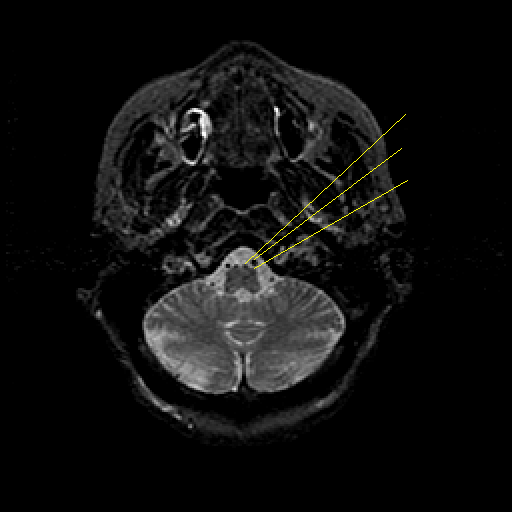

T2-weighted structural MR: Slice 9

Slice 9

Pointers

Labeled